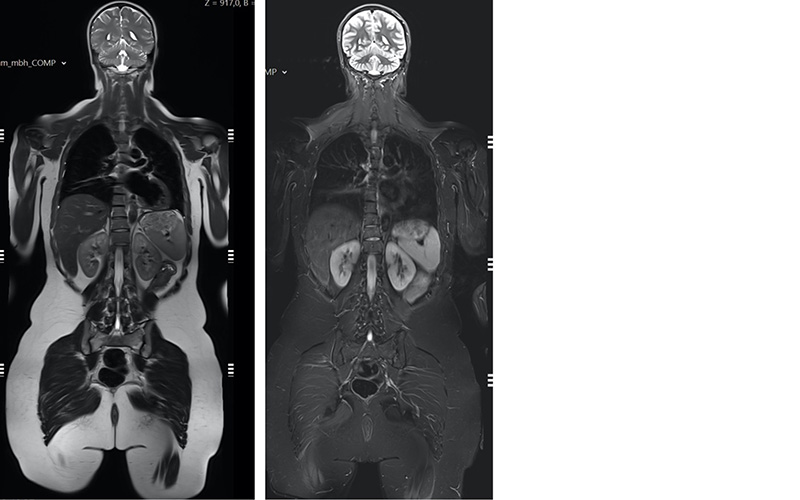

Die Untersuchung erfordert eine spezielle Methodik bei der Bildqualität und Untersuchungszeit optimal aufeinander abgestimmt sind. Dabei ist die Hochfeld-Technik eines 3 Tesla MRT sehr hilfreich, da mit dieser kürzere Untersuchungszeiten und sehr gute Bildqualität kombiniert werden können. Eine einfache Ganzkörperuntersuchung wie sie aktuell ausschnittweise in den zwei Bildern unten zu sehen ist, dauert nicht mehr als 35 Minuten. Bei einer Gesamtuntersuchungszeit von etwa 60 Minuten lassen sich wahlweise einzelne Körperregionen wie Schädel oder Oberbauch mit Bauchspeicheldrüse dazu kombinieren. Kontrastmittelgaben erfolgen nur dann, wenn Auffälligkeiten dazu Anlass geben und dann in der Regel in einer zweiten Untersuchung.